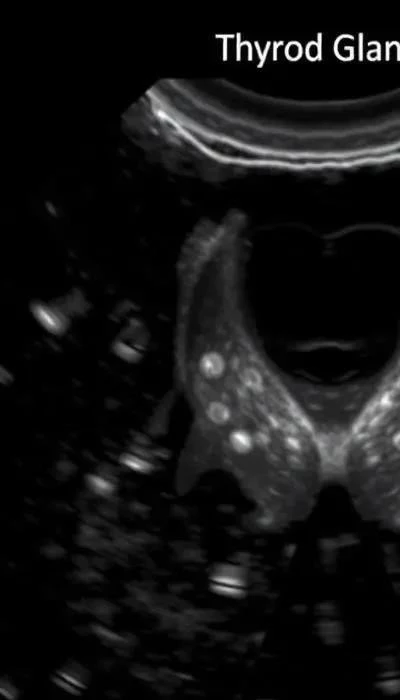

Диагностика гипертиреоза включает в себя несколько этапов. Первым шагом является анализ крови на гормоны щитовидной железы: тиреотропный гормон (ТТГ), Т3 и Т4. При гипертиреозе уровень ТТГ обычно снижен, а уровни Т3 и Т4 – повышены. Ультразвуковое исследование (УЗИ) щитовидной железы позволяет оценить ее структуру и выявить наличие узлов или изменений. В некоторых случаях могут потребоваться дополнительные методы диагностики, такие как МРТ или КТ орбиты глаза (при офтальмопатии), для оценки состояния глазных яблок. Сцинтиграфия щитовидной железы и тест на захват радиоактивного йода также могут быть использованы для определения причины гипертиреоза.